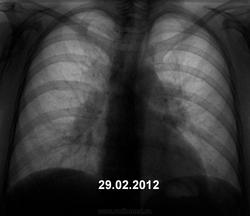

Женщина дисциплинированная, флюорографию не просрочила. Явных жалоб не предъявляет.

Хорошие иллюстрации. Понятно, что будет дообследование (учреждение не имеет особого значения) и верификация.

Мы, на довольно солидном материале убедились, что период даже в 6 месяцев не является гарантией стабильности. Были два случая, где промежуток был даже 4 месяца - "от нормы" до довольно значимой "специфики" (и не только "тубера").

Отдаю голосsmiley за саркоидоз.

да, похоже на саркоидоз

+1. Но, заключение должно быть верифицированно пункцией из доступного лимфатического узла.

Тоже - за медиастинальную форму саркоидоза.

изменений в лёгких   указывает на саркоидоз II стадии.

Я-то вообще сначало не понял ничего! Потом после коментариев почитал, тоже стал склоняться к саркоидозу, но меня смущает отсутствие клинических проявлений, а тень, что рассположена справа у корня мне напоминает увеличенный сосуд.

подобную картину могут давать хронический лимфолейкоз, метастазы различных злокачественных опухолей и др. Здесь необходима  быстрая морфологическая верификация. Игорь Иванович поступил правильно, так как при неблагоприятной эпидемической и социально-экономической ситуации  на постсоветском пространстве туберкулеза много. Я недавно такой случай показывал в игре "Поставь диагноз №5".

1. Это ключевая фраза. 2. Саркоидоз, зачастую не имеет клинических проявлений, поэтому выявляется при профилактических исследованиях. 3. Поглядите внимательно и постарайтесь запомнить, коллега, так выглядят корни при саркоидозе. Практически типичная картина, почти без диф. диагноза.